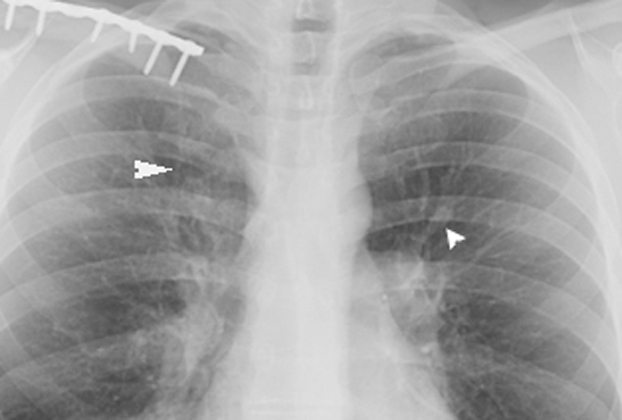

- 左上肺野の浸潤影、気管支拡張像

- 肉芽腫の形成、好酸球の浸潤

アレルギー性気管支肺アスペルギルス症 ABPA